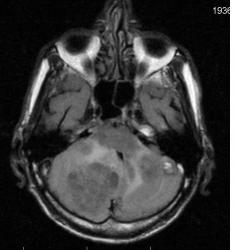

Мужчина 73 лет. За последний год похудел, потерял аппетит. Последний месяц стал плохо ходить, несколько раз падал, неделю назад стал психически не совсем адекватен. Врач - друг семьи, приехавший в гости, настоял на проведении МРТ головного мозга, рентгенографии ОГК и УЗИ брюшной полости. МРТ проводилось в медикаментозном сне, с реанимационным набором наизготовку, по немного укороченным программам. Все закончилось благополучно. Ничего сложного в плане диагностики. Просто не всегда бывает так много и ярко. Есть небольшое продолжение. Потом.

FLAIR:

метастазы